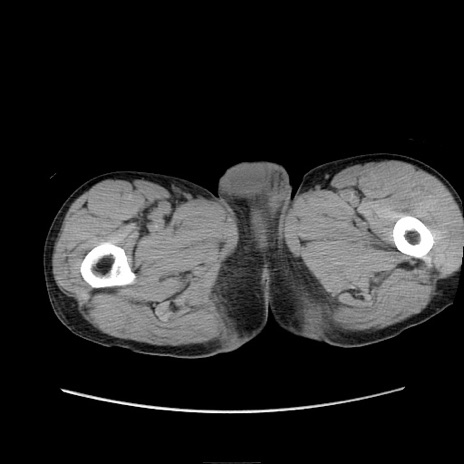

症例11(横断像)

【症例】 60歳代男性

【主訴】 下腹部痛

【現病歴】 本日夜中より下腹部痛の症状認め、受診。

【既往歴】 膀胱癌(膀胱全摘+尿管皮膚瘻術) 、胃癌術後

【身体所見】 BT 35.3℃、PR 58/min、BP 136/98mHg、腹部平坦、軟、腸蠕動音±、ストマ留置あり、左上腹部~正中部に圧痛あり、反跳痛なし。

【データ】WBC 5100、CRP0.01